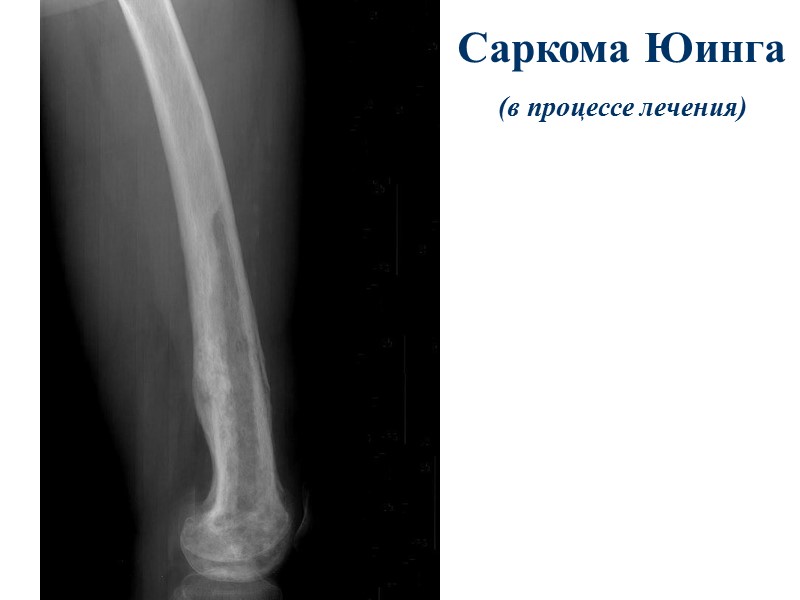

Саркома На Ноге Фото

Саркома На Ноге Фото 113 фотографий